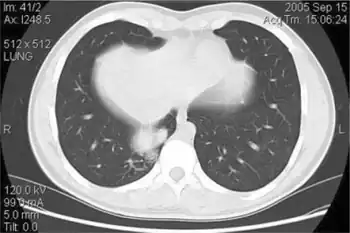

One way to determine if a baby does in fact have a Bochdalek hernia, would be to have a pediatrician perform a physical on the infant. A chest X-ray can also be done to examine the abnormalities of not only the lungs but also the diaphragm and the intestine. In addition to these, a doctor can also take a blood test, drawing arterial blood to check and determine how well the baby is breathing and his or her ability to breathe. A chromosomal test (done by testing the blood) can also be performed to determine whether or not the problem was genetic. The doctors can also take an ultrasound of the heart (echocardiogram) to evaluate the health of the heart.